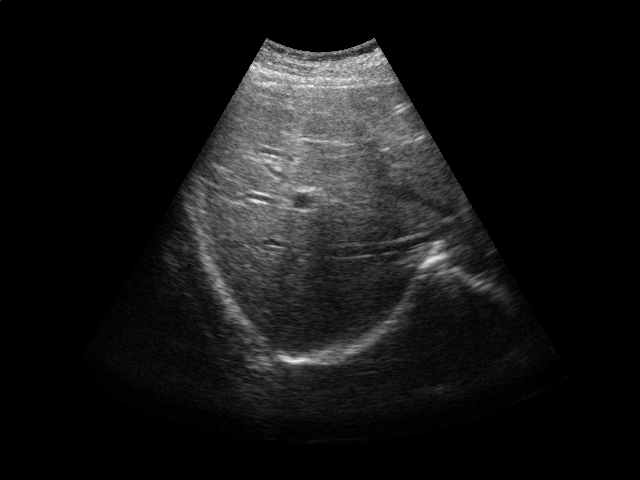

We conduct experiments on five 2D ultrasound image sequences of the human liver acquired during free breathing; example images are shown in Fig. 2. Each sequence contains 640480-pixel images and vary in length between 298 and 371 frames captured at 33 Hz. For a given image sequence, we use each image in the sequence as an input data point for learning a 1D manifold with Laplacian eigenmaps [4]; we use a 9-nearest-neighbor graph with an associated heat kernel of temperature . The 1D embedding learned using an entire sequence of images serves as a reference signal for evaluating our sparse out-of-sample extension versus kernel ridge regression as the baseline. In what follows, we compare the 1D embedding of our sparse out-of-sample extension to the reference signal by computing a correlation coefficient between them. We use kernel ridge regression as a baseline method. Here we train on the first 200 frames and test on the remaining frames. We then compare the results with those obtained by training on all frames, as would be done for retrospective gating.

We first examine the influence of parameters and on the resulting interpolator. Training on the first 200 images of one of the ultrasound image sequences, we compute the correlation coefficient with the reference signal and the number of support vectors versus the error tolerance (Fig. 2). As expected, smaller error tolerance requires more support vectors but also leads to a higher correlation coefficient with respect to the reference signal. Also, a higher kernel ridge regression regularization parameter leads to fewer support vectors. However, stronger regularization also leads to lower correlation coefficients. These results suggest a natural tradeoff between the accuracy and the computational cost of the projection operation.

In the next experiment, we use and . Training on the first 200 frames and testing on the rest of the frames, we report the correlation coefficients and the number of support vectors in Table 1. The number of support vectors for kernel ridge regression is 200 in this case. We then repeat the experiment, training on all the frames. In this case, the number of support vectors for kernel ridge regression is the length of the sequence. We achieve a high correlation for all sequences, with a comparable performance between our sparse interpolator and kernel ridge regression. Comparing the number of support vectors when training on the first 200 frames vs. training on all the frames, we note that the number of support vectors stays roughly the same for a given image sequence. This again suggests that the number of support vectors depends on the low-dimensional embedding’s complexity and not the training set size.